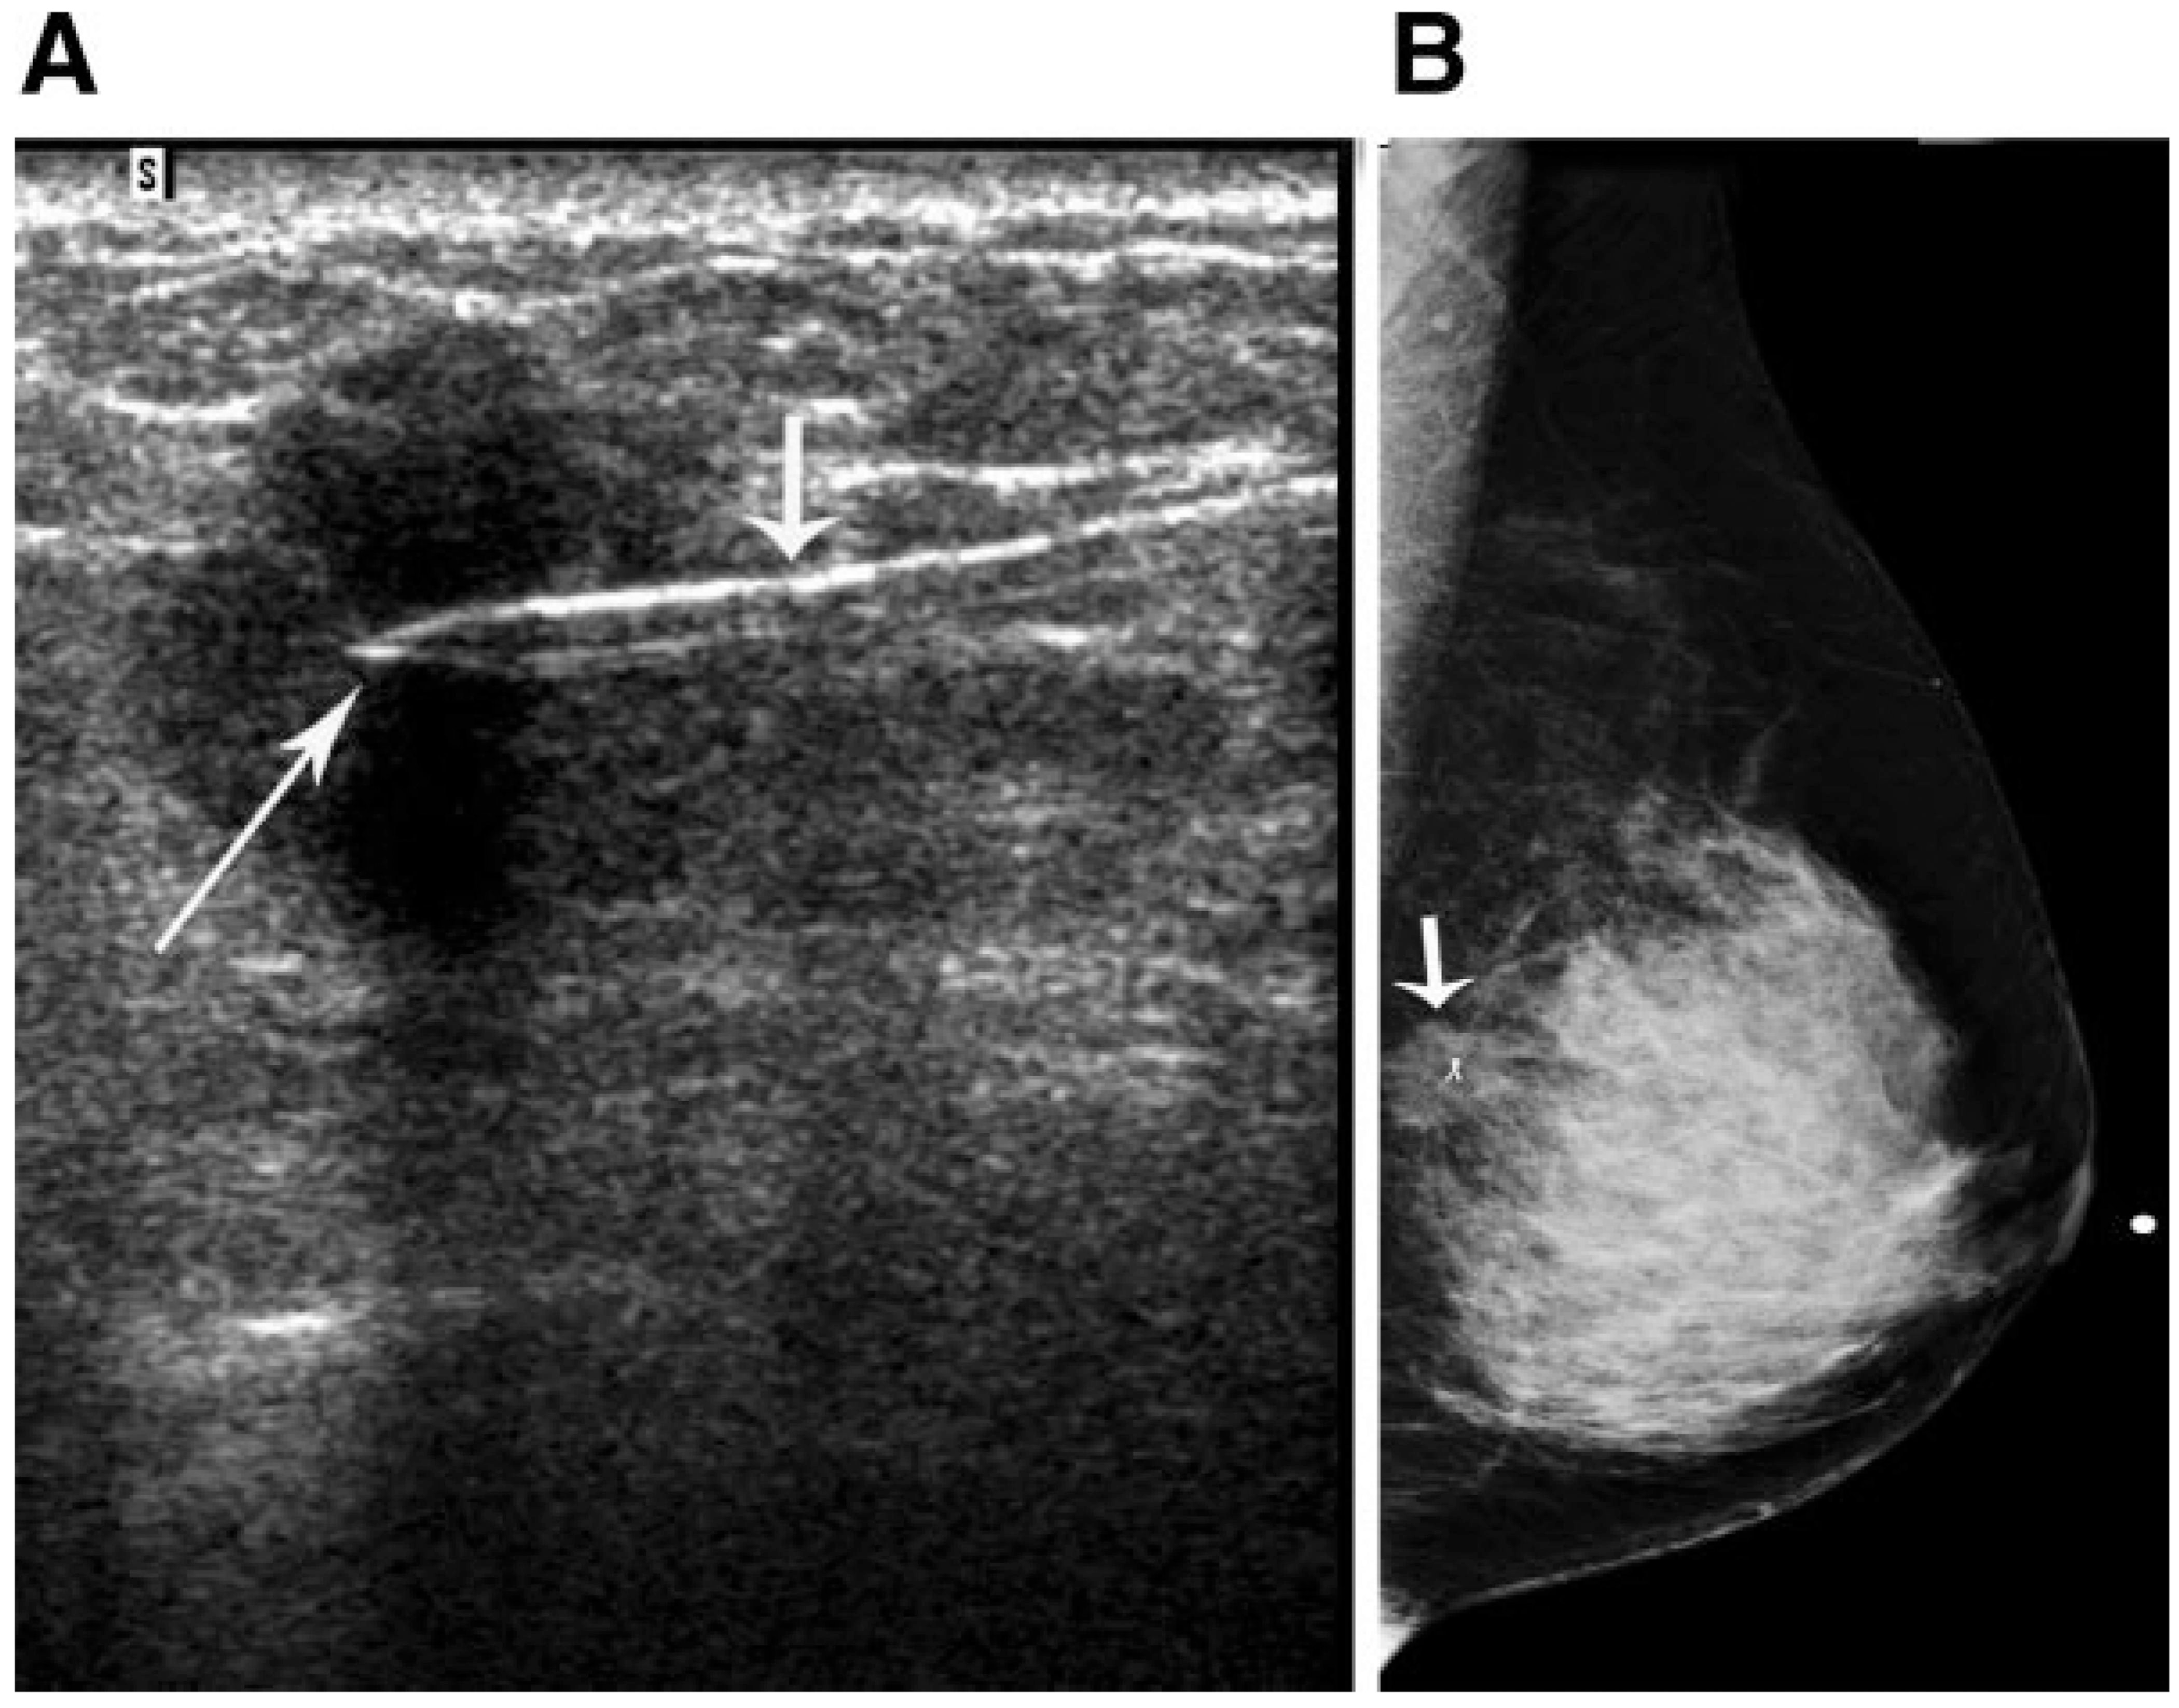

Marker通常放置在瘤床中心,也可根据外科医生和/或放射科医生的判断,放置在瘤床四周。通常在超声引导下放置Marker,并通过术后乳房X光片确认Marker位置(图1)。手术时通过超声识别Marker;在超声不能充分显示Marker或残余肿瘤的患者中,通过术前乳房X线引导下的导丝定位对Marker进行标记。在对残余肿瘤和手术切缘进行病理评估之前,在X光片上确认肿瘤床和所有植入Marker均已成功切除。

图1  48岁女性,浸润性导管癌,放置Marker并通过术后乳房X光片确认Marker位置